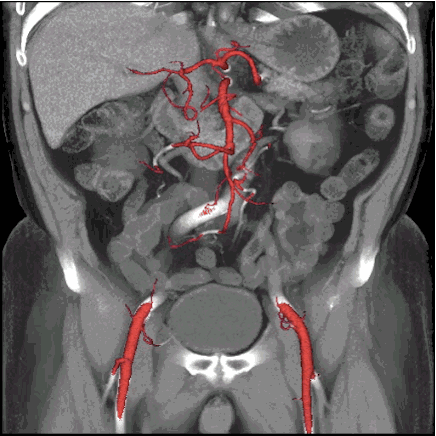

11动态CT下的腹部血管成像